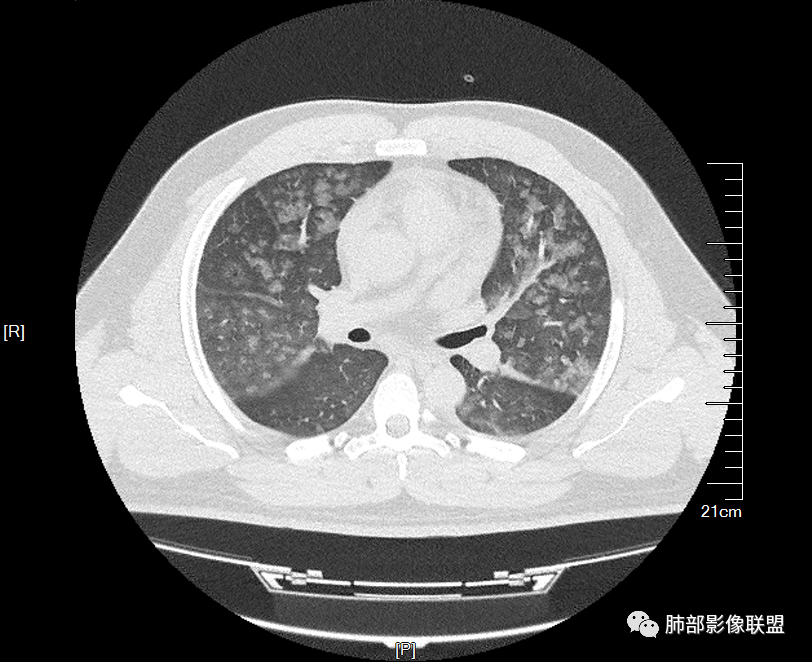

两肺弥漫向心分布的腺泡结节,部分融合,两肺小叶间隔增厚,血肌肝高,考虑肺泡性肺水肿

年轻男性,痛风史,高血压史,肌酐高,左足痛6天入院。胸CT:双肺多发弥漫性磨玻璃结节影,大小不一,部分融合,上中下肺都有,中内带多,胸膜下少。部分血管束略增粗,小叶内间隔、小叶间隔增厚,下肺明显,左室大。叶裂胸膜增厚。临床有痛风,左足痛6天,考虑:心衰、间质性肺水肿?弥漫性肺泡出血?鉴别:MPA,肺肾综合征,痛风结节等。

少量积液,脂肪肝

这里有一点重力趋势

中轴间质稍增厚

中轴间质增厚,小叶间隔增厚,小叶内间质增厚,部分重力作用,双侧对称,胸水,按理淋巴道回流受阻有

肺水肿类病变有

这是急性出血,腔充盈

时间的问题,,为什么呢,就是说,我们一般就是这样,假如这些急性的单纯的非常超急性的,那就是说,肺泡腔充填的,明显的小叶间隔增厚,那我们警惕,不对,这个是不是间质为主的,以小叶为单位间质为主的病变。

如果有出血这个还好解释,肺泡腔充盈的,还有一个弥漫性损伤也可以

损伤的话,我们不知道用的什么样的药物可以这样,然后其他原因所致的肺泡腔的损伤也可以这样。

一开始怀疑吸入的病变,但我看了一下很多全小叶性的,确实小叶核心区域,稍微密度偏高一点那种,我认为就是稍微一点吸收阶段都是那样的,这个我觉得还是肺泡腔充盈为主的病变,不太符合一个吸入的改变。